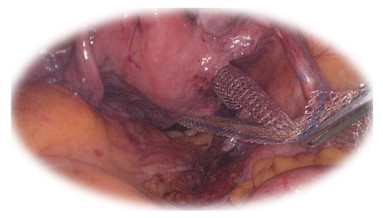

Promontofixația laparoscopică/ robotică:

• Tratament minim-invaziv al prolapsului genital

• Alternativă la chirurgia transvaginală, clasică

• Presupune implantarea unei proteze non- resorbabile pe cale abdominală pentru a corecta prolapsul genital

• Sângerare minimă, recuperare rapidă